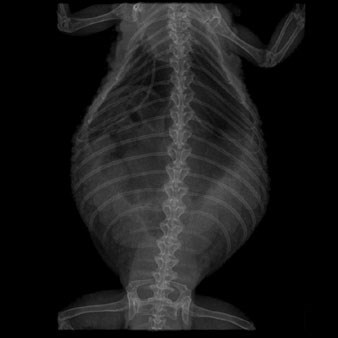

It appears that this female bearded dragon is suffering from hypocalcaemia, with the eggshells – as outlined in the oviducts running down the sides of her swollen abdomen – not being properly mineralised. They would otherwise be more clearly defined in this X-ray.

Image courtesy of the author.